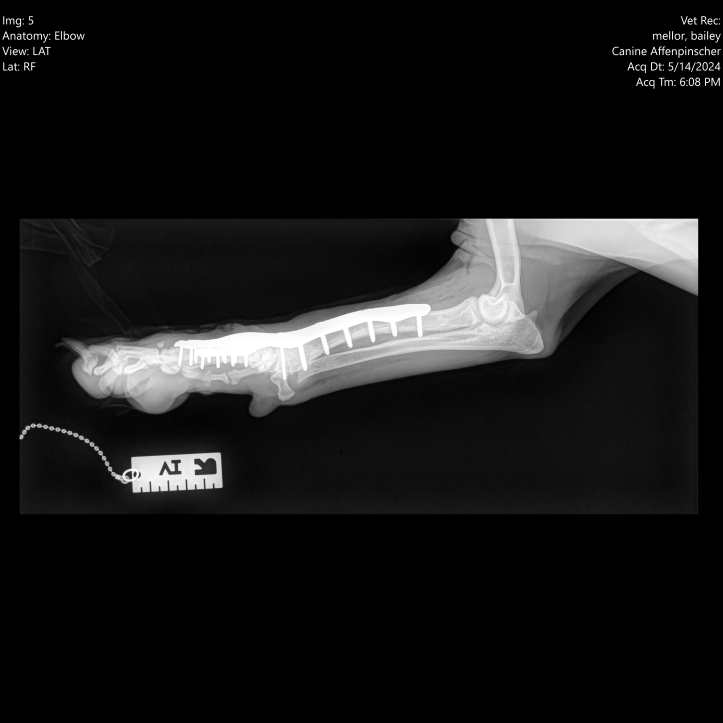

In 2023, Bailey was admitted to Dovecote Veterinary Hospital, where Orthopaedic Specialist James Pratt performed a combined angle correction and partial carpal arthrodesis (PCA) to address the deformity and the resulting arthritis. This advanced surgical procedure involved the use of cutting-edge technology to ensure precision and effectiveness.

bailey1

James, along with a highly trained surgical team, employed 3D-printed guides made by Bill Oxley at Vet3D to make precise cuts in the correct direction. These guides were tailored specifically for Bailey's unique anatomical structure, ensuring optimal accuracy. Following the bone cuts, a custom 3D-printed plate was used to align the bones correctly while the carpal joints fused. This approach not only facilitated the proper alignment of Bailey's carpus, but also promoted successful joint fusion, ultimately relieving the pain associated with osteoarthritis.